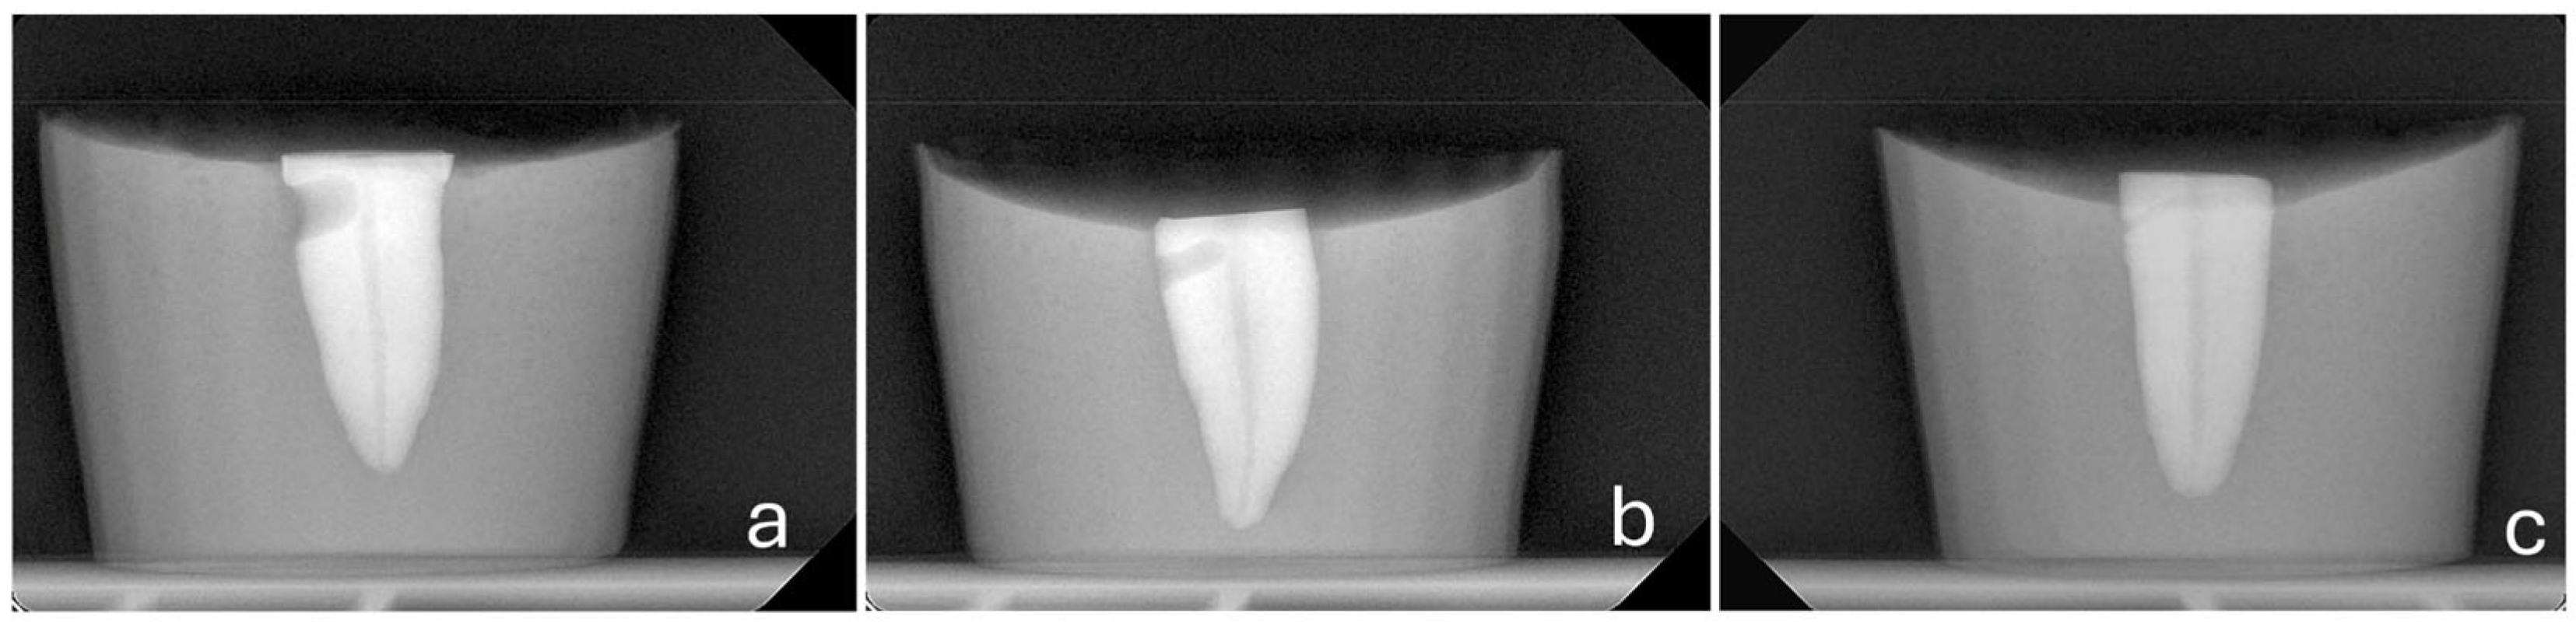

- A consistent perforation diameter. High-speed round burs with diameters of 2.1 mm, 1 mm and 0.5 mm (SS White, Lakewood, NJ, USA) were used for the Groups 3, 4 and 5, respectively. Each bur was used once and then discarded.

- A steady direction of perforation. Teeth were secured in a vise with their buccal surfaces parallel to the horizontal plane. The high-speed handpiece was also fixed in a horizontal position using a custom-made apparatus that allowed only downward vertical movement. Buccal diagonal perforations, starting 3 mm apical to the coronal surface of the teeth, were created under water cooling with a steady angle of 105° between the external surface of the root and the shank of the bur (Figure 2 and Figure 3). A #35-K stainless steel hand file (Dentsply, Maillefer, Ballaigues, Switzerland) inside the root canal prevented the overextension of the perforation to the lingual surface of the root.